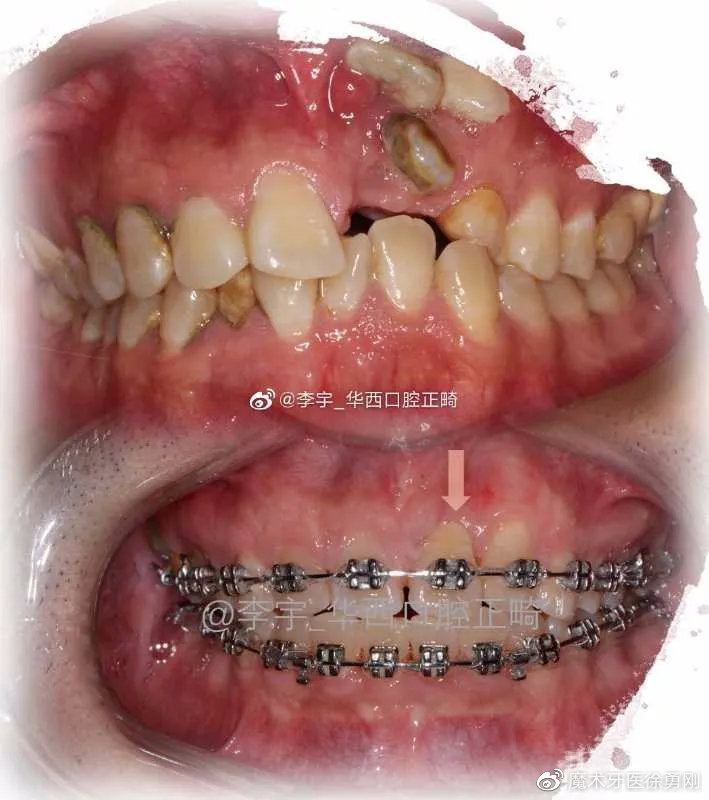

下图就是一个典型的病例,该患者由于正牙期间清洁不良,虽然牙排列整齐了,但却产生了大量的白垩色脱矿病损,影响美观。

有些复杂的病例,多半都是出自正畸大师之手:

在微博上,有很多的正畸大师,经常分享一些复杂病例供同行们评价,赏心悦目。同时,也有不少正畸失败的患者在吐槽、指责Ta们的医生,而且我从微博、贴吧、百度里发现,有一些治疗失败的患者,她们追悔莫及、欲哭无泪的控诉,就跟那些深受“美容冠”伤害的人一样,明显发生了抑郁症倾向。这些失败病例的表现多种多样,有咬合错乱的,有前牙牙根暴露的,有颞颌关节紊乱的,而这些多数都缘于设计失误。